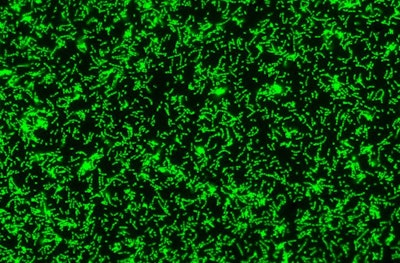

Two overlayed fluorescent microscopy images of S. mutans, the primary bacteria responsible for dental cavities. When S. mutans forms biofilms on the tooth surface, it produces organic acids as metabolic byproducts that dissolve tooth enamel. The green fluorescent image shows S. mutans biofilm mass when grown in the presence of sucrose, a substrate necessary for substantial bacterial attachment and biofilm formation. The red fluorescent image overlayed depicts S. mutans biofilm mass in the presence of sucrose and purified human salivary mucins. Mucins are key structural components of mucus and saliva that play an important role in host defense. Image courtesy of Nicole Kavanaugh of MIT and the American Society for Microbiology.

"We found that salivary mucins don't alter S. mutans' growth or lead to bacterial killing over 24 hours. Instead, they limit biofilm formation by keeping S. mutans suspended in the liquid medium," stated Dr. Frenkel, who is also a doctoral student in Ribbeck's biological engineering lab at MIT, in a press release. "This is particularly significant for S. mutans, because it only causes caries when it is attached or in a biofilm on the tooth's surface."

The viscoelastic properties of mucus and saliva are attributed to mucins, large glycoproteins that play a key role in host defense and maintaining a healthy microbiome. Human salivary mucins protect teeth from dental cavities, which are primarily caused by S. mutans colonization.